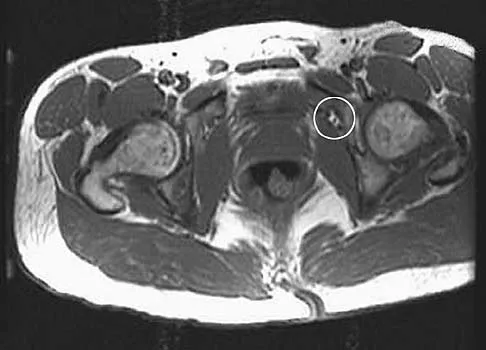

An axial T1-weighted MRI scan of the pelvis is shown in Figure 35. Which of the following structures is enclosed by the circle?

Explanation